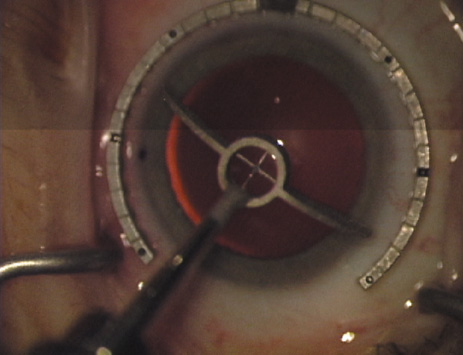

Case 2 is a 79-year-old woman who presented with a very dense left cataract. Her refraction was recorded at −2.25 +2.75 × 125 with a difficult end point. Her manual keratometry and topography measurements were consistent and revealed slightly less than 1.75 D at 120 degrees. Because of the questionable refraction, greater value was placed on the corneal measurements. Based upon the cataract nomogram, the plan was for paired LRIs of 40 degrees to be placed over the steep 120-degree axis (Figs. 1219).

Fig. 12. In this left eye, the steep meridian is at the 120-degree axis and has been delineated by opposing limbal marks. The upper left hand ink mark represents the 6:00 position for orientation. (Reprinted from Hardten DR, Lindstrom RL, Davis EA. Phakic Intraocular Lenses: Principles and Practice. Thorofare, NJ: SLACK Incorporated, 2004, with permission.)

Fig. 13. The incision is begun 20-degrees to one side of the centering mark. (Reprinted from Hardten DR, Lindstrom RL, Davis EA. Phakic Intraocular Lenses: Principles and Practice. Thorofare, NJ: SLACK Incorporated, 2004, with permission.)

Fig. 14. The incision is completed. (Reprinted from Hardten DR, Lindstrom RL, Davis EA. Phakic Intraocular Lenses: Principles and Practice. Thorofare, NJ: SLACK Incorporated, 2004, with permission.)

Fig. 15. Total arc length equals 40 degrees. (Reprinted from Hardten DR, Lindstrom RL, Davis EA. Phakic Intraocular Lenses: Principles and Practice. Thorofare, NJ: SLACK Incorporated, 2004, with permission.)